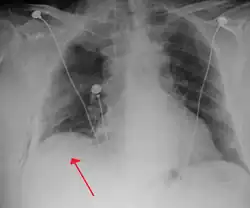

![]() Radiografía de tórax de un neumotórax izquierdo a tensión | ||

El neumotórax es la acumulación de aire en la cavidad pleural, conformada como un espacio hallado entre los pulmones y el tórax.[2][5][6] Los síntomas suelen comenzar con dolor agudo y punzante localizado en el pecho y disnea.[1] En una minoría de casos, se forma una válvula unidireccional producida por el tejido dañado que provoca un aumento patológico del espacio pleural. Esto se conoce como neumotórax a tensión, una causa de choque obstructivo debido al bloqueo de la circulación sanguínea. Esta situación puede conllevar una disminución gradual de la cantidad de oxígeno en sangre y de la presión sanguínea que, de no ser tratado, puede resultar mortal.[2] Con rara frecuencia, el neumotórax puede darse en ambos pulmones en lo que se conoce como neumotórax bilateral.[7]

Neumotórax a tensión

Se considera que existe neumotórax a tensión cuando un neumotórax (espontáneo primario, espontáneo secundario, o traumático) conlleva una disfunción significativa de la capacidad para respirar o afecta de manera importante la circulación sanguínea.[35] Este tiende a ocurrir en situaciones clínicas específicas como la administración de ventilación mecánica, durante una RCP, tras un proceso traumático grave o en personas con enfermedades de las vías respiratorias.[20] Se trata de una emergencia médica que puede requerir de tratamiento inmediato sin la búsqueda de un diagnóstico más exhaustivo.[20][35]

Las manifestaciones más comunes en personas con neumotórax a tensión son el dolor torácico agudo y la insuficiencia respiratoria, que a menudo se presenta inicialmente a través de un pulso cardíaco elevado (taquicardia) o un aumento de la frecuencia respiratoria (taquipnea). Constantes hemodinámicas como el oxígeno en sangre o la presión sanguínea pueden hallarse igualmente disminuidas (propiciando una situación de hipoxia e hipotensión, respectivamente). Estas son las manifestaciones del choque obstructivo. En ciertos casos es posible observar una desviación de la tráquea hacia el lado no afecto. Durante la auscultación, uno de los pulmones puede presentar una disminución de los ruidos respiratorios respecto al otro. Con menor frecuencia puede darse cianosis (coloración azul de la piel por la falta de oxígeno), alteración del nivel de conciencia, hiperresonancia a la percusión en el lado afectado o dolor en el epigastrio.[35][37]